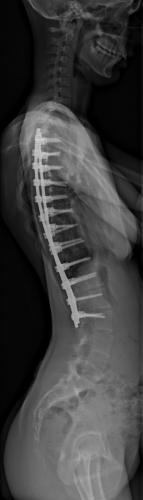

Images de scolioses opérées 16 janvier 202418 janvier 2023 par Damien Scoliose Thoracique et lombaire 1 Radio pré-opératoire de Face Radio pré-opératoire de Profil Radio à 1 an de recul de Face Radio à 1 an de recul de Profil